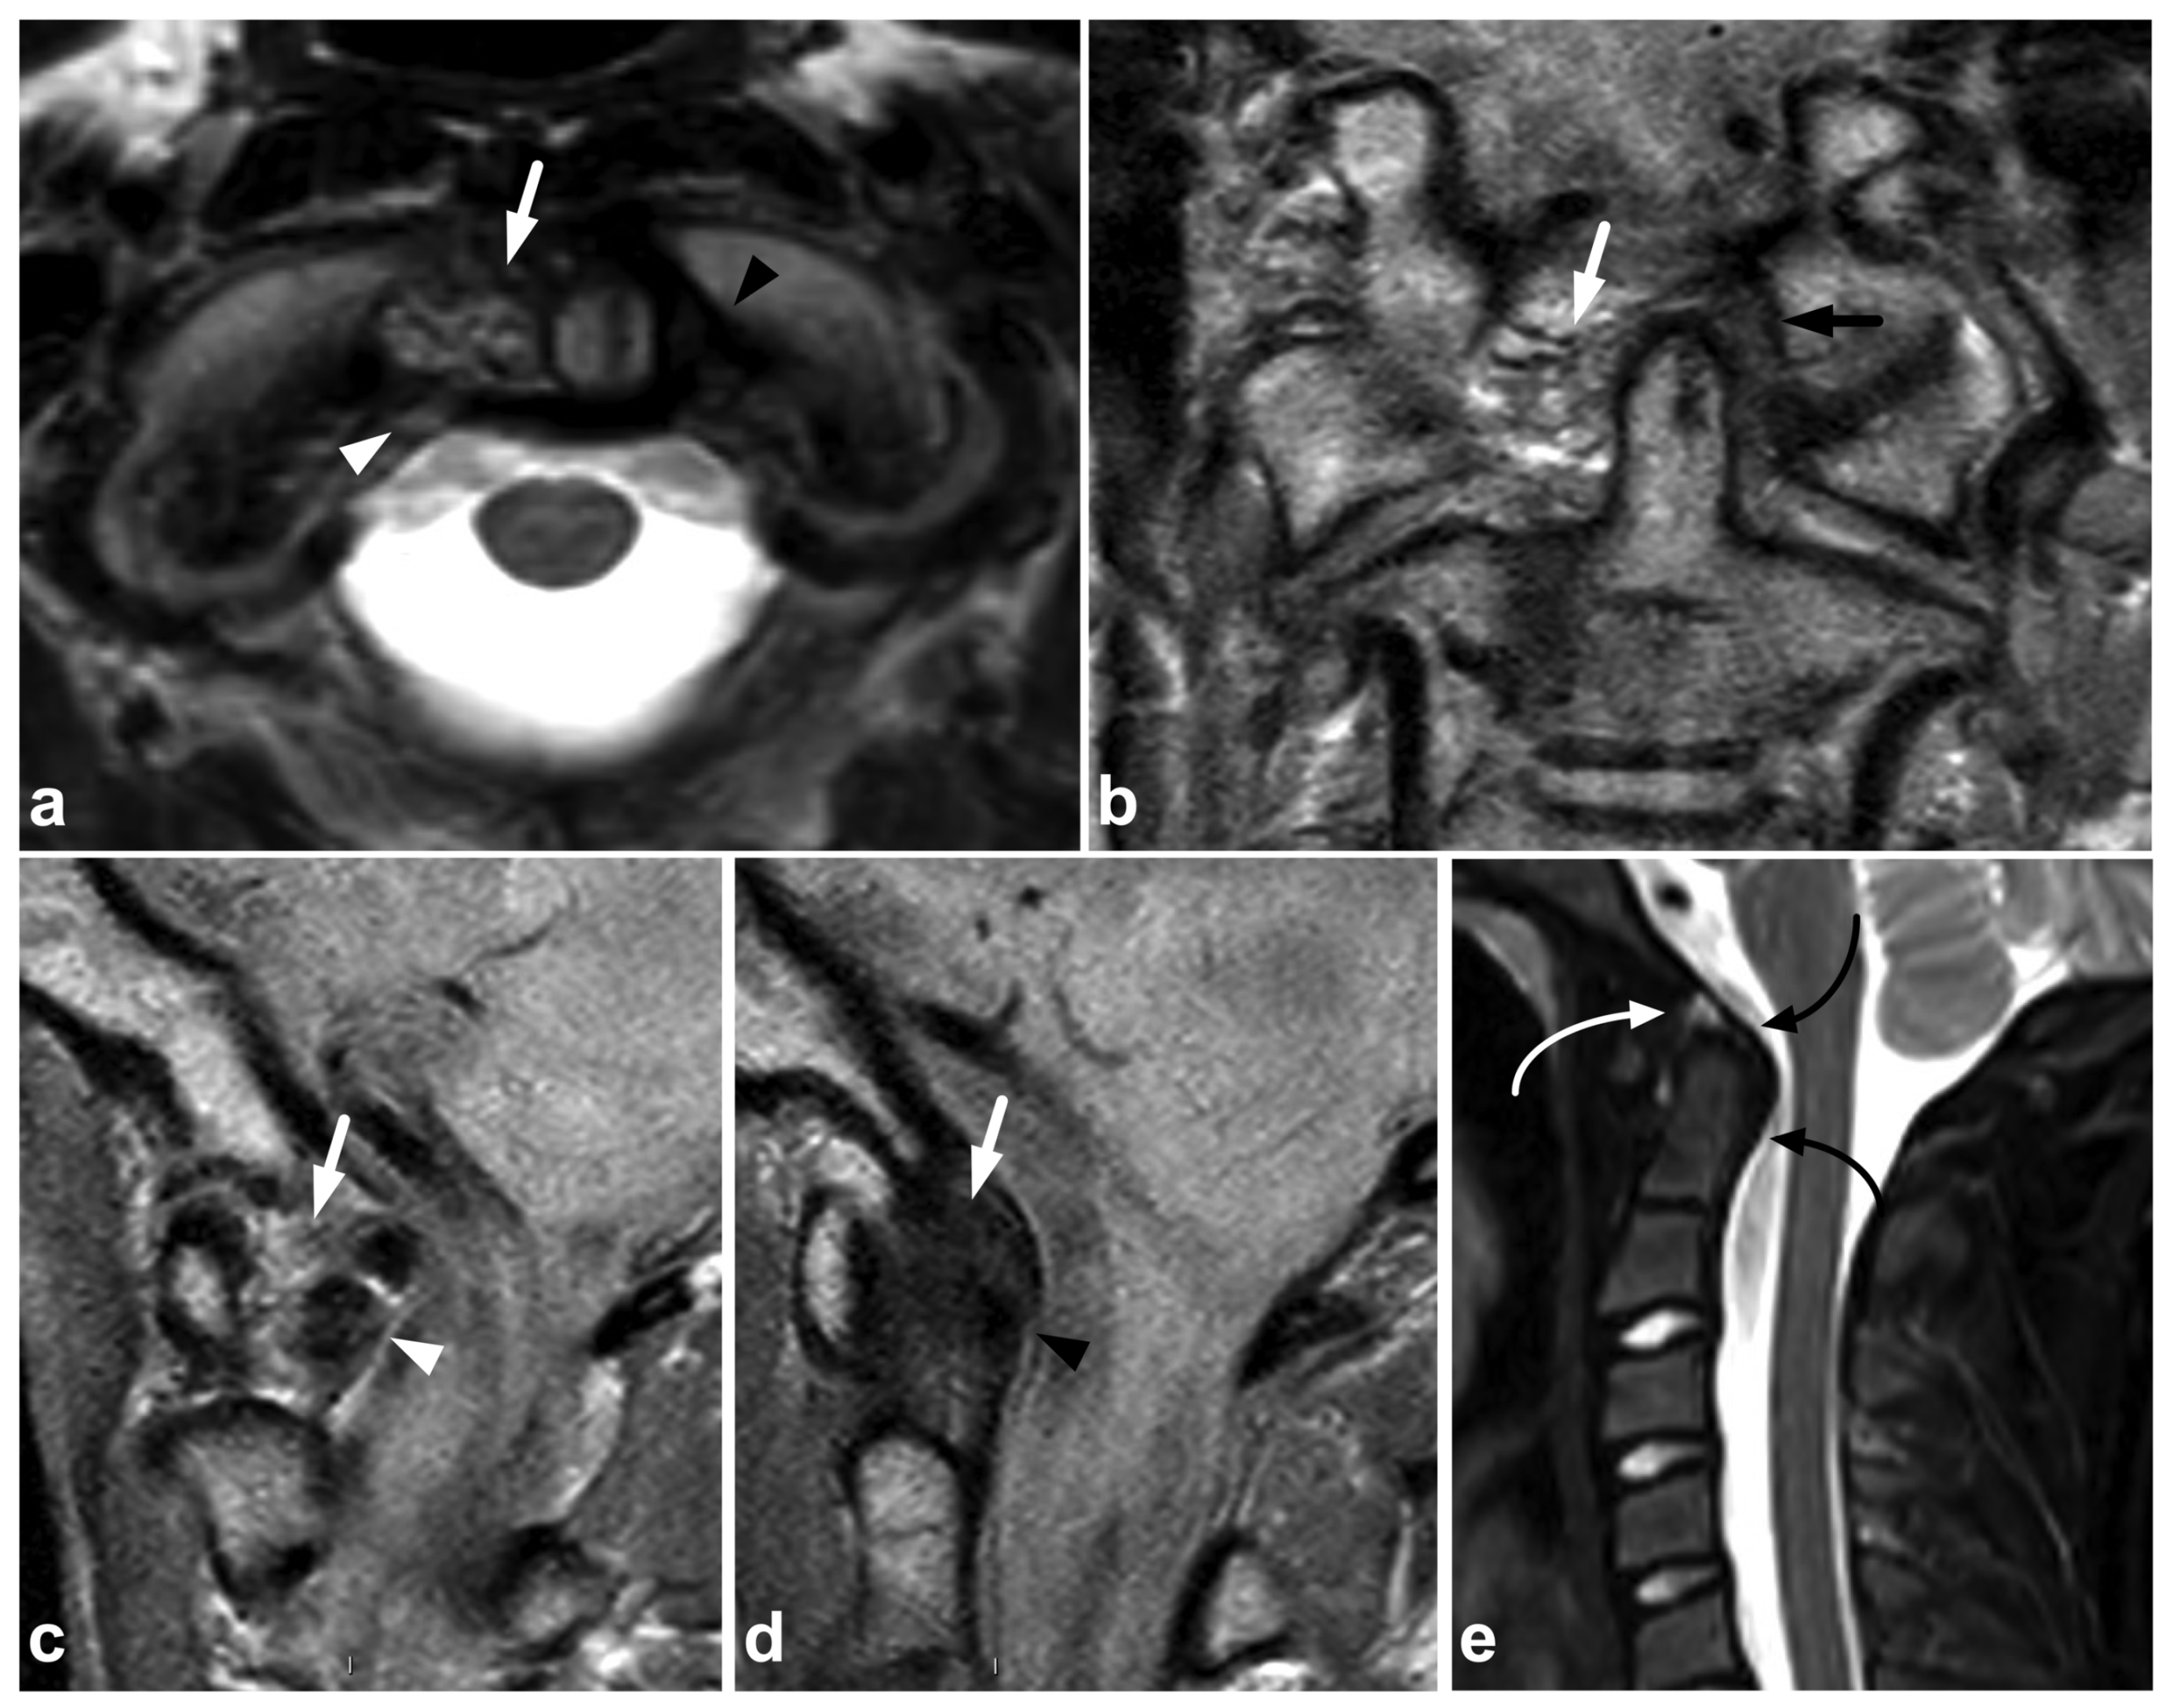

The craniocervical and atlantoaxial joints are mobile structures allowing flexion–extension movement and rotation of the head. The joints’ biomechanics and the importance of different stabilizing structures are not yet completely understood. The joint capsules, the alar ligaments, and the transverse ligaments are crucial to stability [33,38,39]. The role of the tectorial membrane is more controversial, but it might also be of importance in preventing overextension [33,40]. Injury to the stabilizing joints or ligaments may lead to instability. Isolated soft tissue injuries and avulsion fractures without complete joint dissociation (Figure 4) may occur. All the joints and ligaments mentioned above are visible on MRI. A higher field strength and dedicated proton density- and T2-weighted sequences with a smaller field of view may help to delineate these small structures better [41]. Figure 8 demonstrates a case with an upper cervical spine ligament injury.

Figure 8.

(a) Axial T2-weighted. (b) Coronal PD-weighted. (c) Right-sided off-midline sagittal PD-weighted. (d) Sagittal PD-weighted. (e) Sagittal STIR. A 12-year-old male, football injury. The right alar ligament (white arrows) is torn. The right side of the transversal ligament is thickened and heterogenous, suggesting a partial distension injury (white arrowheads). The left alar ligament (black arrows) and the central and left-sided portions of the transversal ligament (black arrowheads) are intact. The tectorial membrane is unharmed (curved black arrows), but the apical ligament of the dens is poorly visible, probably torn (curved white arrow). Apparent asymmetry of the lateral atlantodental intervals is seen, but there are no signs of occipitocervical or atlantoaxial joint capsule disruption.